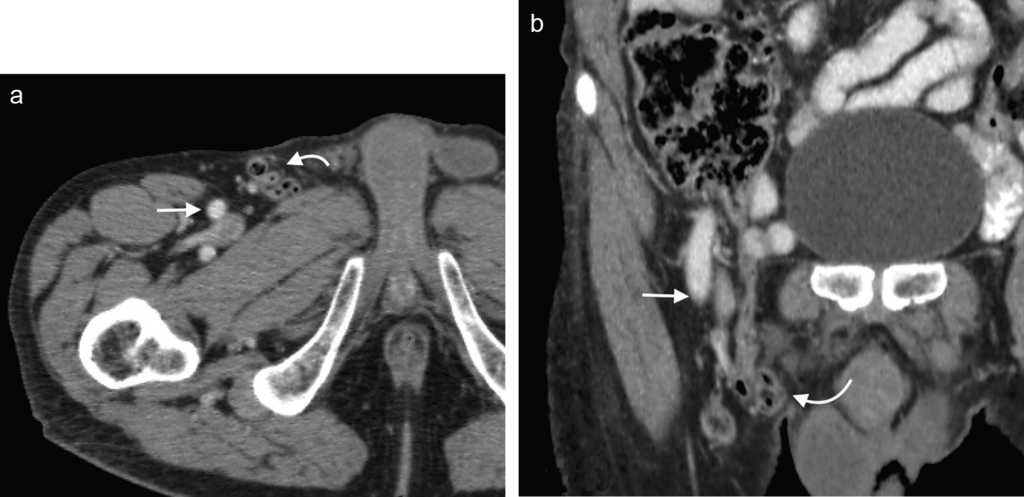

La hernia inguinal indirecta atraviesa el anillo inguinal interno, recorre el conducto y emerge a trav??s del anillo externo, sobresaliendo superior y externamente a los vasos epig??stricos inferiores. Puede extenderse por el conducto esperm??tico o el ligamento redondo hacia el escroto o los labios mayores, respectivamente. Es posible ver el cuello del saco herniario en el anillo inguinal profundo1 (fig. 1). Un hallazgo que ayuda a su caracterizaci??n es el signo del gancho. Este debe su nombre a la forma c??ncava que adopta la arteria epig??strica inferior en el plano axial en su curso proximal, al ser comprimida por una hernia indirecta6.

En lo que respecta a la directa, esta se ubica por encima del ligamento inguinal y medial a los vasos epig??stricos inferiores, y en general es adquirida. Su incidencia aumenta con la edad por el debilitamiento de la fascia transversal en el tri??ngulo Hesselbach1. Suele ser m??s frecuente en hombres y est?? menos asociada a la estrangulaci??n de las asas, posiblemente porque en general no atraviesa todo el curso del canal4 (fig. 2). El contenido del canal inguinal es comprimido lateralmente, mientras que su grasa se ubica como una luna creciente, produciendo el signo de la semiluna creciente (un hallazgo que ayuda a la caracterizaci??n de estas hernias)7.

En la TCMD el cuello del saco herniario se identifica como una estrecha protrusi??n a trav??s del anillo femoral, en direcci??n caudal al origen de los vasos epig??stricos inferiores y de forma medial a la vena femoral com??n, que frecuentemente aparece comprimida por el saco herniario (fig. 3). A veces en la evaluaci??n cl??nica resulta dif??cil distinguir una hernia femoral de una inguinal, por lo que la TCMD tiene un rol importante en su diferenciaci??n y valoraci??n del contenido2. Lo m??s com??n es visualizar asas de intestino delgado dentro del saco herniario, pero tambi??n se puede encontrar el ap??ndice dentro de este canal. Esto ??ltimo es poco frecuente (1% de los casos) y recibe el nombre de hernia De Garengeot9 (tabla 2).

Su diagn??stico espec??fico se puede hacer si en la TCMD de pelvis se visualiza el intestino herniado entre los m??sculos pect??neo y obturador externo con obstrucci??n del intestino delgado sin una causa aparente3 (fig. 4).